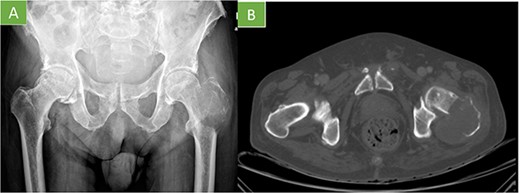

The radiological image showed an osteolytic lesion that had destroyed the intertrochanteric region of the left femur (Fig. 1A). A computed tomography (CT) was performed and showed the femur lesion with an associated soft tissue mass (Fig. 1B). In the staging studies, other detectable metastases were ruled out.

(A) X-ray pelvis AP view: geographic lytic insufflating expansive lesion centered in the intertrochanteric region of the left femur that destroys the cortex with poorly defined borders in certain locations. Soft tissue mass associated. The tumor matrix shows thin septum reaching 9 cm in longitudinal axis. (B) Axial CT: lytic lesion with cortical destruction at trochanteric level.